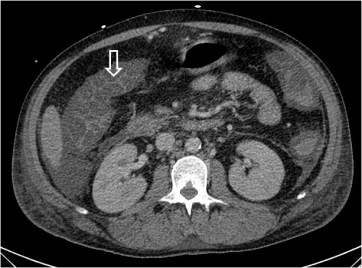

Signo de edema o inflamación severa del colon, de cualquier etiología, visto en TC. Corresponde al engrosamiento de la pared del colon con retención del contraste oral entre las haustras engrosadas (flevchas), aunque el signo también puede estar presente en TC sin contraste. Fue descrito inicialmente en la colitis por Clostridium difficile (colitis pseudomembranosa), pero después se ha demostrado que no es específico, pudiendo estar presente en otras colitis infecciosas por otros gérmenes (Salmonella, citomegalovirus,…) en colitis isquémica, en vasculitis (lupus) e incluso en el edema relacionado con cirrosis.

Otras imágenes del signo en otro paciente. Cortes axial (derecha) y sagital (izquierda), donde se observa la afectación del ángulo hepático del colon.

El artículo que describe la inesecificidad del signo es de Macari, M y cols: The accordion sign at CT: a non specific finding in patients with colonic edema. Radiology 1999; 211: 743-746. Se puede consultar en: http://pubs.rsna.org/doi/full/10.1148/radiology.211.3.r99jn32743.